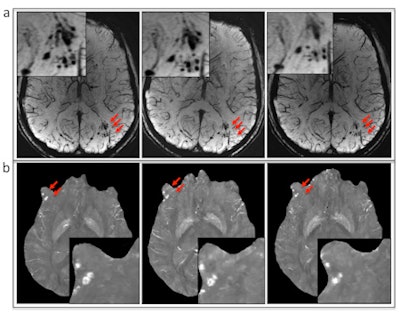

(A) Susceptibility-weighted MRI and (B) quantitative susceptibility mapping show the evolution of microbleeds (arrows) in a patient who had follow-up imaging. Image courtesy of RSNA."Even though previous studies have shown that SWI is superior to GRE in the detection of hemorrhage, its clinical application in military clinics is still limited," the authors noted. "Our results indicate that for the identification of the presence or absence of cerebral microhemorrhages, SWI should be the method of choice clinically."

Additionally, the sooner an injured solider received an MRI, the greater the chance of finding cerebral microbleeding. SWI detected microhemorrhages in 24% of patients who underwent imaging within three months after their injury, compared with 18.4% for those scanned after three to six months, 7.6% for those scanned six to 12 months later, and 5.2% for those scanned more than a year later. The effect could be due to changes in iron deposits in the brain over time, making it more difficult to detect the microhemorrhages, according to the authors.